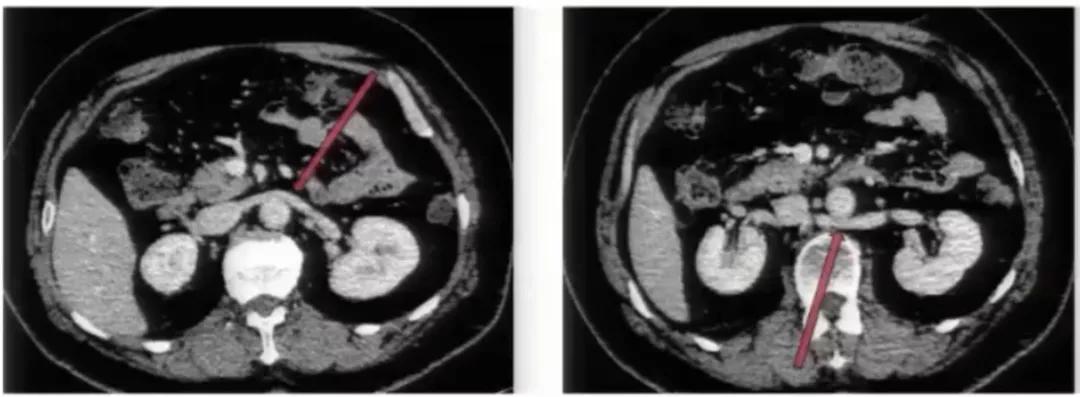

图1:腹膜后方下腔静脉处于腹主动脉左侧;左肾静脉出左肾门后,汇入下腔静脉路径缩短

主动脉后型左肾静脉

主动脉后型左肾静脉是一种少见的左肾静脉先天发育异常,有两种分型:完全性主动脉后型,即左肾静脉走行于主动脉的后方,并汇入下腔静脉。环主动脉型,即左肾静脉分两支,分别位于主动脉前后方。

临床意义:

①避免肾脏手术时,左肾变异静脉误切、误扎;

②左肾静脉主干或分支走行于主动脉和脊柱之间,受到两者挤压引起左肾静脉血回流障碍,称后胡桃夹综合征,引起血尿或蛋白尿;

③左肾癌时,变异的左肾静脉可出现癌栓。

影像表现:

完全性主动脉后型左肾静脉:左肾静脉主干出肾门后横行走行,经过腹主动脉后方汇入下腔静脉,少数左肾静脉向右下走行,横行经过左髂总动脉后方汇入左髂总静脉。

环主动脉型左肾静脉:左肾静脉主干出肾门后分成前、 后两支,前支走行正常,后支可在同水平或斜向右下走行,经过腹主动脉后方汇入下腔静脉,另有少见两条左肾静脉独立自肾门发出。主动脉后左肾静脉主干或分支受压,近端增粗,其属支包括左侧生殖静脉、肾上腺静脉及腰静脉曲张。